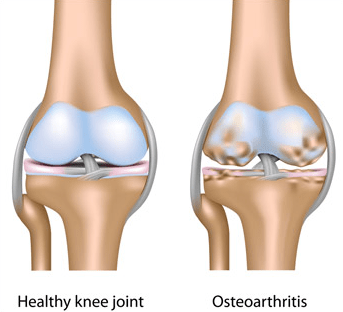

مفصل جایی است که دو استخوان بهم میپیوندند. انتهای این استخوانها با بافت محافظی به نام غضروف پوشانده شده است. آرتروز سبب تجزیه این غضروف میشود و باعث می شود استخوانهای مفصل به هم ساییده شوند. این مسئله میتواند باعث درد، سفتی و سایر علائم شود.

آرتروز هنگامی رخ میدهد که غضروفهایی که انتهای استخوانهای مفاصل شما را پوشش میدهند به تدریج خراب شوند. غضروف یک بافت سفت و لغزنده است که حرکت مفصلی تقریباً بدون اصطکاک را امکانپذیر میکند. در نهایت، اگر غضروف کاملاً فرسوده شود، استخوان روی استخوان ساییده میشود.

آرتروز غالباً به عنوان بیماری “سایش” شناخته میشود. اما علاوه بر تجزیه غضروف، آرتروز کل مفصل را تحت تأثیر قرار میدهد؛ باعث ایجاد تغییراتی در استخوان و تحلیل رفتن بافتهای پیوندی مفصل شده و عضله را به استخوان متصل میکند. همچنین باعث التهاب پوشش مفصلی میشود.

آرتروز زانو

آرتروز زانو که در محافل علمی و دانشگاهی بیشتر با نام استئوآرتریت و استئوآرتروز شناخته میشود، یک بیماری تخریبی پیشرونده در ناحیه مفاصل زانو است که علائمی همچون درد و محدودیتهای حرکتی را اعمال میکند.

مانند آرتروز مفصل ران، آرتروز زانو نیز میتواند در یک یا هر دو زانو ایجاد شود. سن، ژنتیک و آسیبدیدگی زانو ممکن است در آرتروز زانو نقش داشته باشد.

درمان آرتروز زانو بستگی به مرحله بیماری دارد.

در این عارضه، مقداری از بافت غضروفی استخوانها در محل مفصل زانو تخریب میشود. این اتفاق موجب میشود استخوانها با فاصله کمتری نسبت به یکدیگر در فضایی با حداقل غضروف و حداکثر ساییدگی قرار بگیرند.